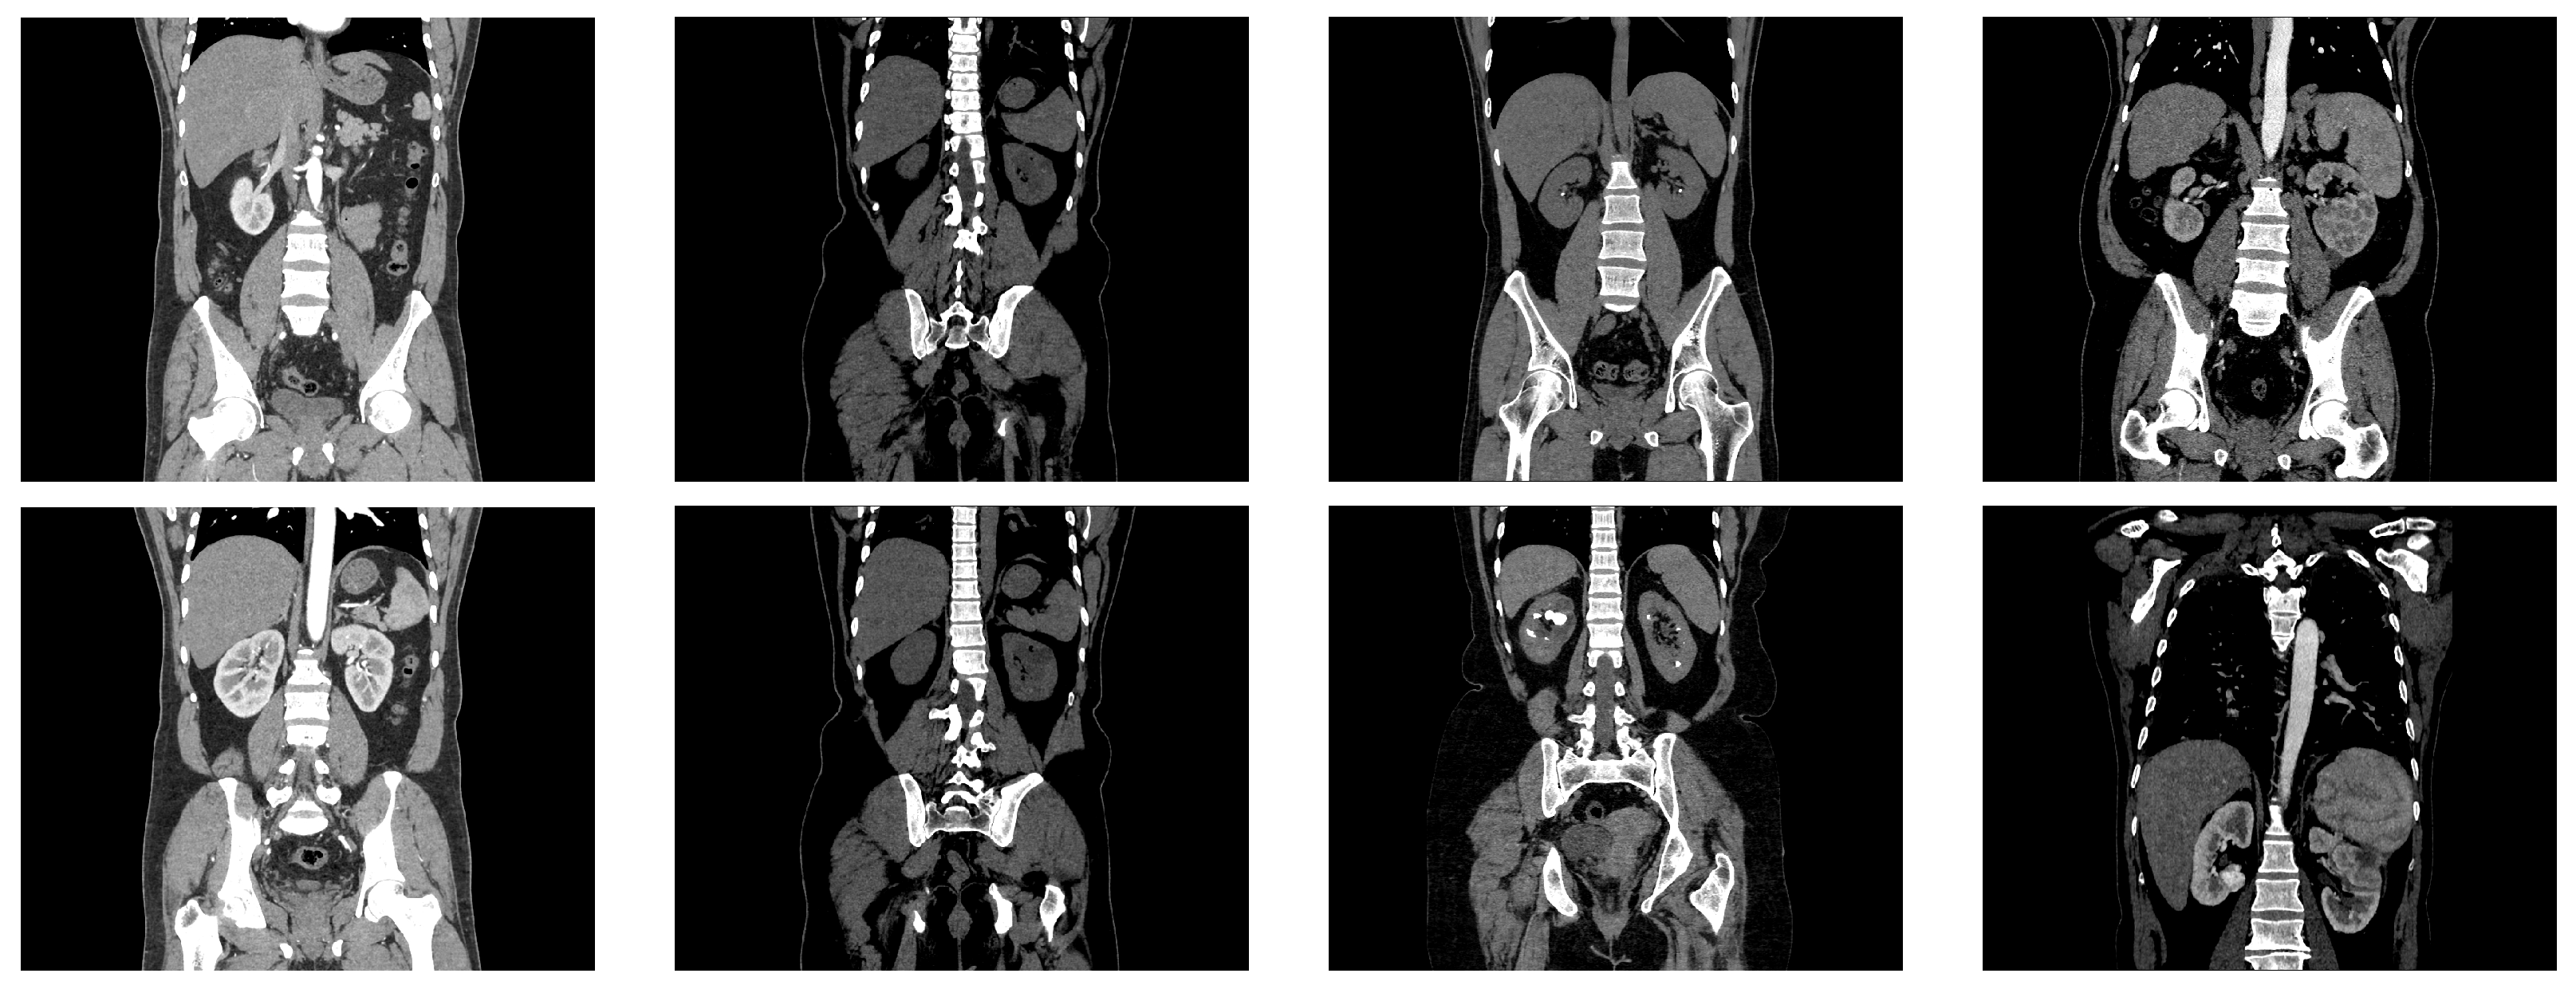

Figure 3 shows several samples from the dataset, with two scans of each dataset class.

Figure 3.

Examples from the kidney dataset. The two images in the first column represent CT images of normal kidneys, the two images in the second column depict kidneys with cysts, the images in the third column represent CT images of kidneys with stones, and the images in the last column depict kidneys with cancer.

Images of the dataset were selected from axial and coronal anatomical planes with and without contrast for the entire abdomen. The data format was DICOM, and the images were converted to JPG format. The dataset originally contained 12,446 samples and, after removing duplicate samples, this was reduced to 11,929 images. Table 2 shows the distribution into the four classes.